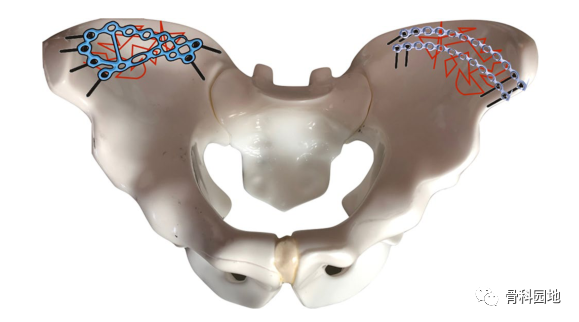

双侧粉碎性髂骨骨折的示意图。观察单个跟骨板与使用 2 个传统重建板的同一区域的封闭区域。即使有2个重建板,覆盖面积也较小(左侧)